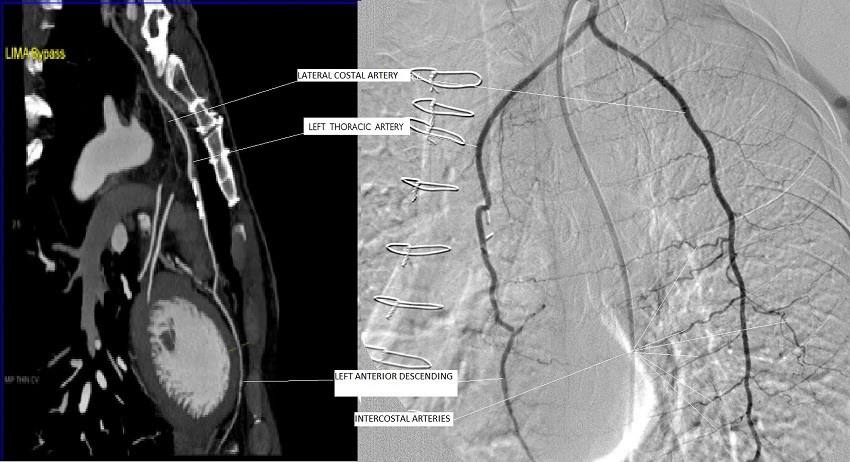

Case 1: 65-year-old female patient, underwent triple CABG three months ago, applied to us with angina pectoris appearing after 50-100 m of walking. She had been under medical treatment of acetylsalicylic acid 100 mg and metoprolol 100 mg. Effort test of the patient whose physical examination and resting electrocardiography (ECG) were normal unveiled ST depression (Table 1). Coronary angiography performed in the patient revealed a well-developed LITA side branch at a distance of 2-2.5 cm from the origin of LITA (Figure 1). The accessory branch, being one and a half times the diameter of LITA, was extending to the lateral thoracic wall, where it was making anastomoses with lateral intercostal arteries and thus supplying blood to anterior and posterior side of the lateral thoracic wall. It was detected that this accessory thoracic artery, the LCA, was stealing a large part of the myocardial blood flow to lateral thoracic wall. The LCA was obliterated via coil embolization (Figure 2). The patient's effort capacity had improved and no ST segment change was observed in the effort test performed one month after the coil embolization of the lateral costal artery.

A study conducted on cadavers demonstrated that the LCA shows variation at the proximal part of the LITA (15%)[6]. It could be present unilaterally or bilaterally, and it has a diameter close to the LITA. The same study pointed out the increased possibility of steal phenomenon due to these side branches in case the LITA was used as a vascular graft for the coronary revascularization[6]. Henriquez-Pino et al.[6] showed that the LITA arises directly from the left SCA in 70% of the cadavers and that the internal thoracic artery gives LAC branch more distally on the left side. Other arteries accompanying the LCA at the proximal part of the LITA are the suprascapular artery, transverse cervical artery, inferior thyroidal artery, and ascending cervical artery. In the all three cases we present, the LCAs of varying diameter were anastomosing with lateral intercostal arteries. We have detected the undivided LCA in only three cases within seven years. In a long period of follow-up, due to probability of existence of asymptomatic patients and symptomatic patients applying to other institutions, the exact rate of prevalence of undivided LCA for our center couldn't be determined. In one of our cases, a female with breast-feeding history, LCA diameter was greater than the LITA diameter (Figure 1). After evaluating the coronary angiographies of 103 patients who underwent CABG surgery, Sutherland et al.[10] found that the LCA was present in 30 (29%) patients, either unilaterally or bilaterally. They showed that 25 of these were extending to the 2nd intercostal space, while the remaining 5 extended to the 5th intercostal space.